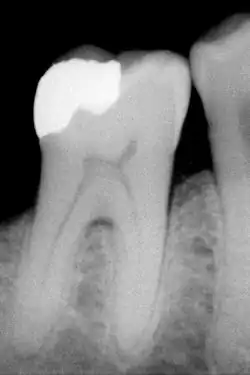

Die klassische Amalgamfüllung ist indiziert bei Füllungen der Kavitätenklassen I und II. Weitere plastische Füllmaterialien sind Komposite (in der Praxis als Kunststoff bezeichnet), Compomere, Glasionomerzement und andere Zemente sowie die Goldhämmerfüllung. Von diesen sind nur die Komposite bei adhäsiver Befestigung im kaubelasteten Bereich indiziert. Compomere und Glasionomerzemente können für definitive Füllungen im nicht kaubelasteten Bereich verwendet werden. Alle übrigen Zemente finden heute nur noch als provisorische Füllmaterialien Verwendung.

Ist die Karies entfernt, muss die Dentinwunde verschlossen werden. Bei flachen Kavitäten kann das durch eine Lackierung (beispielsweise mit Copalharz) geschehen, bei tieferen Kavitäten geschieht es durch eine Zementunterfüllung (meist Glasionomerzement oder Zinkphosphatzement). Bei adhäsiv befestigten Füllungen geschieht die Versorgung der Dentinwunde durch Bonding.

Wenn die Karies so tief geht, dass sie in unmittelbare Nähe der Pulpa vordringt, muss vor dem Legen der Unterfüllung durch ein Calciumhydroxid-haltiges Medikament die Dentin-Neubildung angeregt werden. Diese Abdeckung der Pulpa durch das Medikament nennt man Überkappung; wenn die Dentinschicht über der Pulpa noch erhalten ist, spricht man von indirekter Überkappung, ist sie eröffnet, spricht man von direkter Überkappung. Für die direkte Überkappung hat sich nach verschiedenen Studien Mineral Trioxid Aggregat (MTA) als dem Calciumhydroxid überlegen erwiesen.[1]